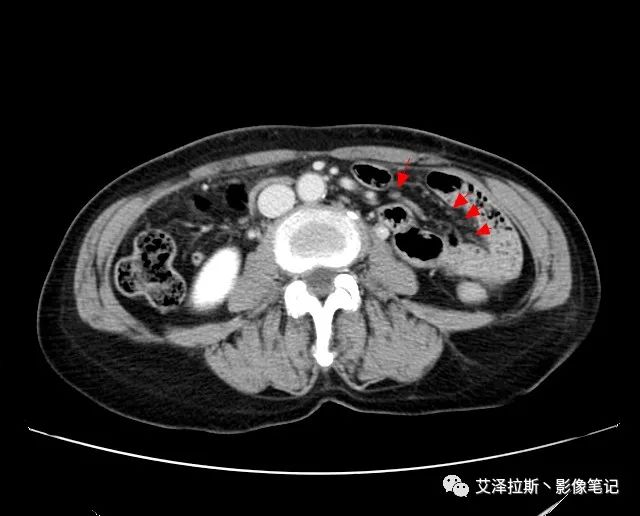

以下為累及的區(qū)域淋巴結(jié),共計15個區(qū)域:

【影像所見】 胃竇部狹窄,胃壁環(huán)形增厚,小彎側(cè)見一巨大潰瘍,周圍伴“環(huán)堤征”,漿膜面不完整,胃周脂肪見網(wǎng)格狀條索影,病灶與肝臟左葉、胰腺鉤突脂肪間隙消失,增強(qiáng)掃描病灶明顯強(qiáng)化。引流區(qū)內(nèi)約15個區(qū)域淋巴結(jié)受累。

【診斷意見】 胃竇部胃癌(T4N3期) 該病例腫塊突破漿膜層,與肝臟左葉、胰腺鉤突分界不清,脂肪界面消失,定為T4期; 受累及的淋巴結(jié)為15個區(qū)域,定為N3; 有無遠(yuǎn)處轉(zhuǎn)移尚不明確,所以M期暫時無法確定。